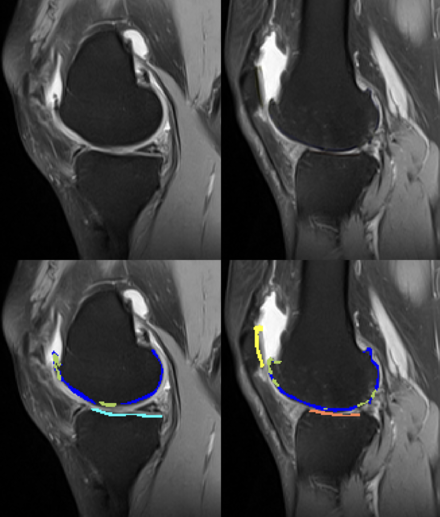

- RMN: indicat în stadii incipiente sau când se suspectează leziuni asociate (menisc, cartilaj, LIA).

RMN gonartroza avansata